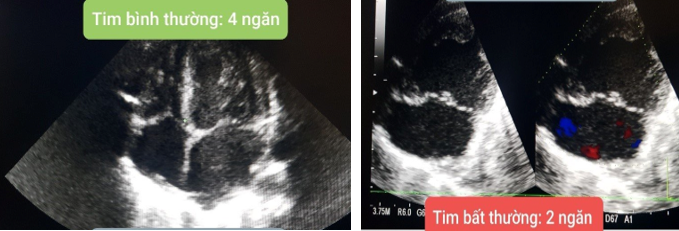

Tim

bẩm sinh là bệnh có thể chẩn đoán sớm và chính xác bằng Siêu âm

tim. Siêu âm tim là một thăm dò chẩn đoán bằng cách sử dụng sóng siêu âm tần số

cao (siêu âm) để có được những hình ảnh động về tim và những cấu trúc liên quan

đến tim. Đây là một kỹ thuật không xâm lấn, không sử dụng bức xạ và không xảy

ra tác dụng phụ

Ảnh

minh họa

2. Một số hình ảnh tim bất

thường